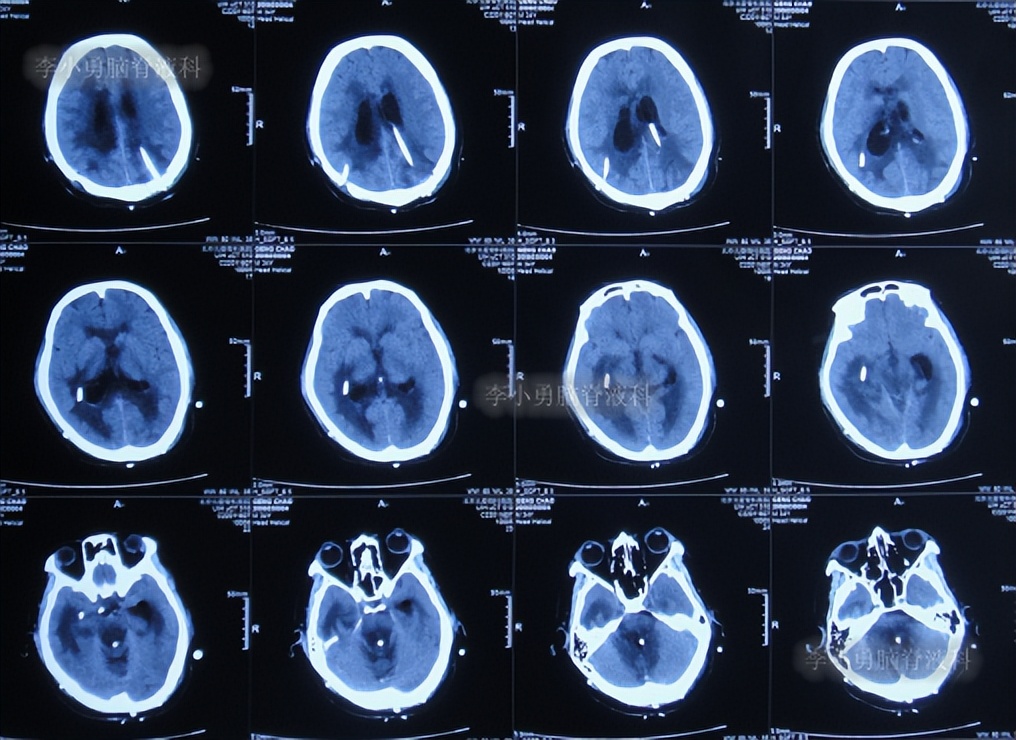

出院后1年半期间,仍时有视物重影的症状,并未给予处理,但到2019年9月27日(脑室腹腔分流术后1年零6个半月),出现头晕,恶心呕吐,视物重影加重,5天后因症状无缓解,就诊于当地的河南省临颍县某医院,查脑CT示脑积水(图-1);给予腰穿检查示颅内压力高220mmH2O。

图-1:2019年10月3日头颅CT